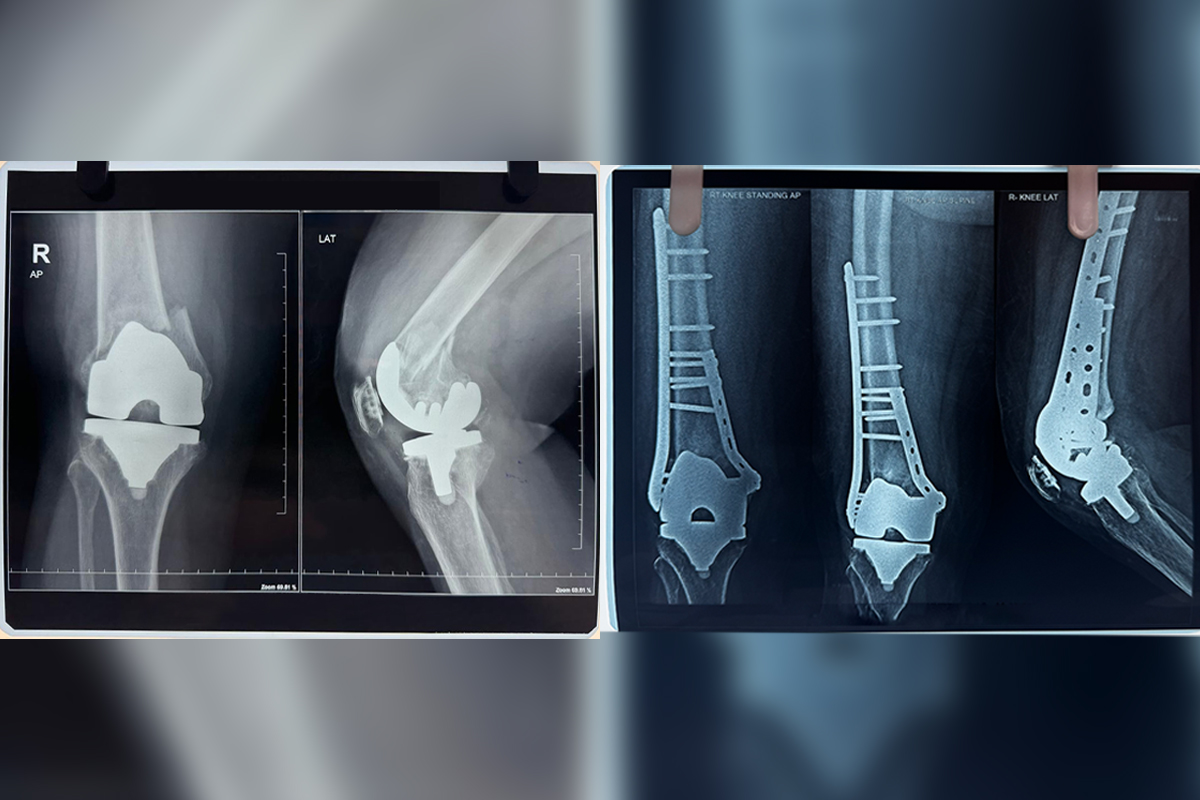

Revision Knee Replacement

Revision Knee Replacement is a surgical procedure to replace a previously implanted artificial knee joint that has worn out or failed...

Periprosthetic Fractures

Periprosthetic Fracture refers to a broken bone near an artificial joint, often requiring surgical intervention for repair and stabilisation...